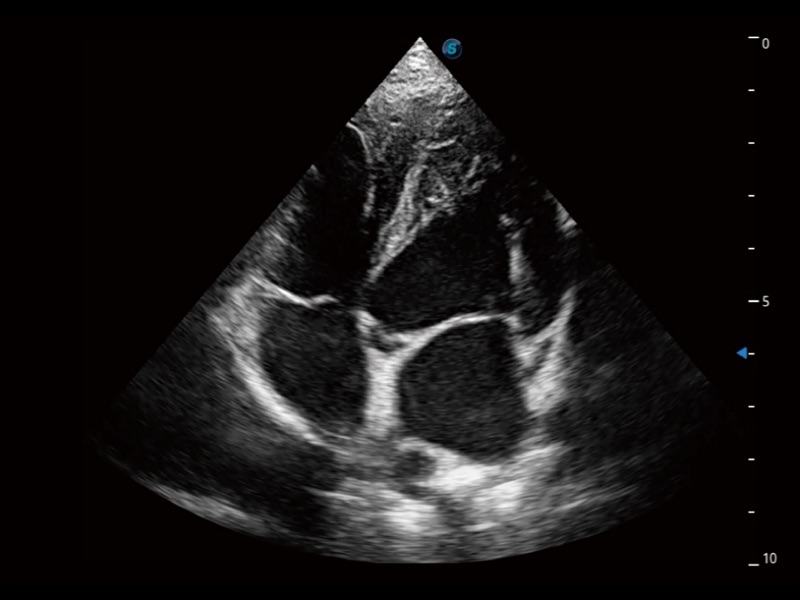

ProPet 70 进一步提升了微米成像算法,更加注重对基础原始图像的还原和保留,在有效减少斑点噪声、增强组织边界显示的同时,避免过度优化丟失真实的解剖信息。

ProPet 70专为动物医生设计,对不同的动物体型和生理结构作出了针对性的优化。通过动物影像专用软件,可满足个性化的应用需求,帮助动物医生获得更精确的诊断数据。